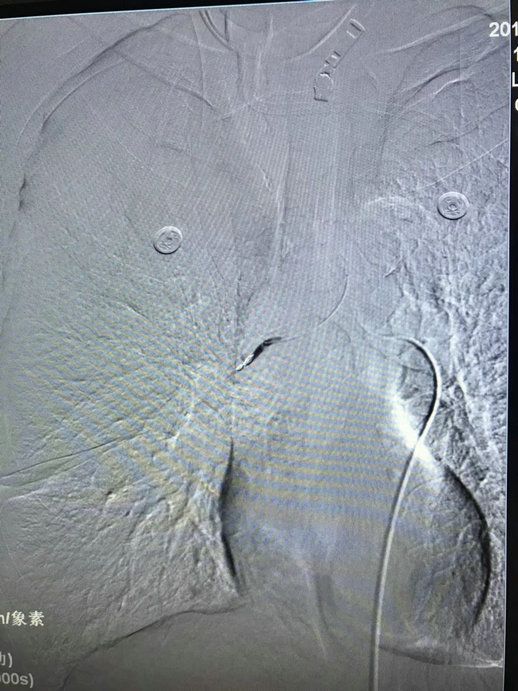

5月15日上午,我院内四科收住了一名反复大咯血的肺癌患者,该患者多次药物治疗后效果不佳,科主任严亚军联系介入科进行急会诊,经与介入科李渊博主治医师反复讨论后,决定急诊行支气管动脉造影+栓塞术。支气管动脉造影显示:右下支气管动脉远端及小分支造影剂弥散。随微导管超选聚乙烯醇栓塞微球+弹簧圈栓塞,再次造影显示:造影剂弥散消失。经术后一周随访,患者再未出现咯血,精神状态良好。